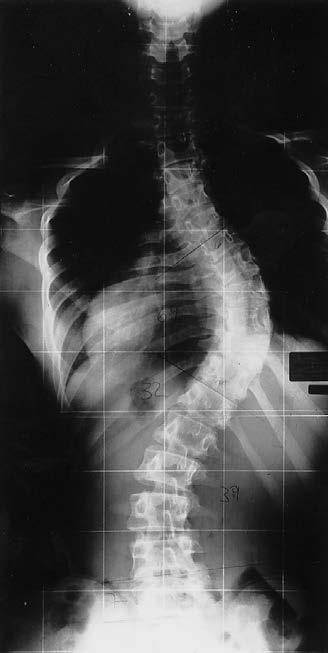

Früher definierte man die Skoliose als teilstrukturelle Seitverbiegung der Wirbelsäule, welche nicht mehr vollständig aufgerichtet werden kann (Heine und Meister 1972, Meister 1980, Asher und Burton 2006, Weiss und Moramarco 2013a). Im Gegensatz zu den Skoliosen bekannter Ätiologie (angeborene Skoliose, neurogene Skoliose, myogene Skoliose, Skoliose bei Stoffwechsel- oder Systemerkrankungen, Skoliosen bei seltenen Syndromen) tritt die idiopathische Skoliose (Abbildung 1) ohne ersichtlichen Grund vor Einsetzen der Skelettreife auf (Heine 1980, Perdriolle und Vidal 1985, Weiss und Moramarco 2013a). In 80-90 % der Fälle handelt es sich um eine idiopathische Skoliose. Eine asymmetrische Rumpfsilhouette im Stand deutet auf eine Skoliose hin. Der Vorbeugetest zeigt die strukturelle Komponente der Skoliose durch den in dieser Haltung hervortretenden Rippenbuckel oder durch den dadurch in Erscheinung tretenden Lendenwulst. Durch die ventral verdrehten Rippen auf der thorakalen Konkavseite entsteht zusätzlich ein sogenannter ventraler Rippenbuckel. Die Diagnose einer Skoliose erfolgt mittels einer Röntgenaufnahme der gesamten Wirbelsäule im Stehen (Abbildung 2). Im Zeitalter des digitalen Röntgens ist es möglich, bei optimaler Einstellung in der Verlaufskontrolle mit einer „kleinen“ Aufnahme und reduzierter Belichtungszeit auszukommen (Abbildung 3). Bei Patienten mit einer Körpergröße über 170 cm sind allerdings in der Regel zwei Teilaufnahmen anzufertigen und dann aneinanderzufügen.

Abbildung 2: Ganzaufnahme im Stehen mit Teilen des Skelettschädels und Beckens. Unter Verwendung der „direct radiography“ (DR) kann man heutzutage allerdings Kinder und Adoleszente bei optimaler Einstelltechnik auch unter Einblendung des Strahlenfeldes auf die absolut notwendige Region (Region of Interest/ROI) fast immer auf eine DR-Platte bringen, ohne weitere Aufnahmen zu machen (Weiss und Seibel 2013).